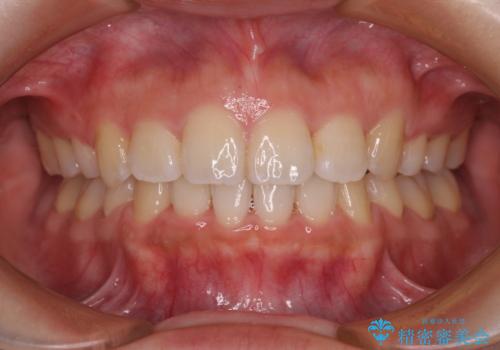

インビザライン単体で、左右ともに移動の難しい位置に歯根のある犬歯を整えるのは困難と判断し、補助装置を併用することとしました。

ディープバイトや奥歯の咬み合わせなど、インビザライン矯正では限界がありワイヤー装置での治療に及ばない仕上がりとなりました。

ただし、患者様としては八重歯や、それに伴う唇の閉じにくさが改善されたとのことで、納得いく状態での治療終了となりました。